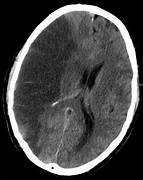

AVC Ischémique avec transformation hémorragique

Publié par : Kamal nadifi